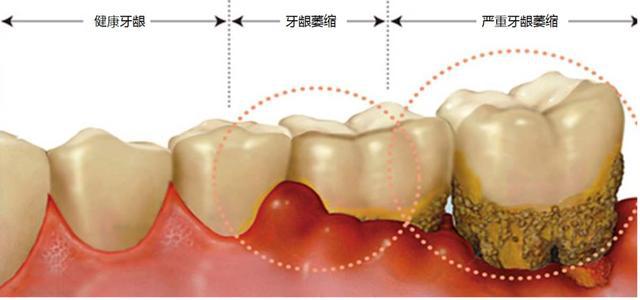

为啥牙龈会萎缩?

1、生理性的萎缩

那就是随着年龄的增长自然老化的结果,这种叫生理性萎缩,是不需治疗的,但可以通过保健延缓。

2、病理性的萎缩

如果年轻人出现牙龈萎缩,一般都是病理性的萎缩。

牙结石,牙龈炎,牙周炎,食物镶嵌都是刺激致使牙龈萎缩的原因。

然后牙槽周围病变,牙槽骨吸收后,附着在牙槽骨上的牙龈就会松动,出现牙龈萎缩。

牙龈萎缩可以恢复吗?

让人比较难过的是,牙龈一旦萎缩了就很麻烦,是不可逆的,只能控制!

牙周炎引起的牙龈萎缩在获得专业治疗之后能得到控制,但已经被破坏的牙龈组织和已经出现的牙龈萎缩是不可逆的。

但即使牙龈萎缩无法恢复,治疗也需要及时进行,只有控制病情发展,才能防止牙龈继续萎缩,避免牙齿松动甚至脱落的悲剧。

牙龈萎缩导致牙齿松动,最终导致患牙脱落。